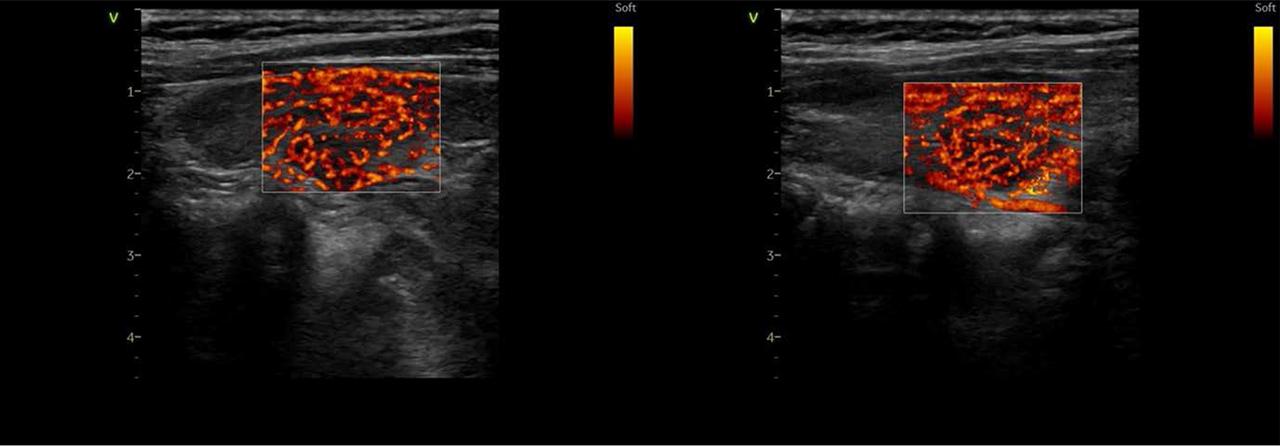

FIGURE 1.